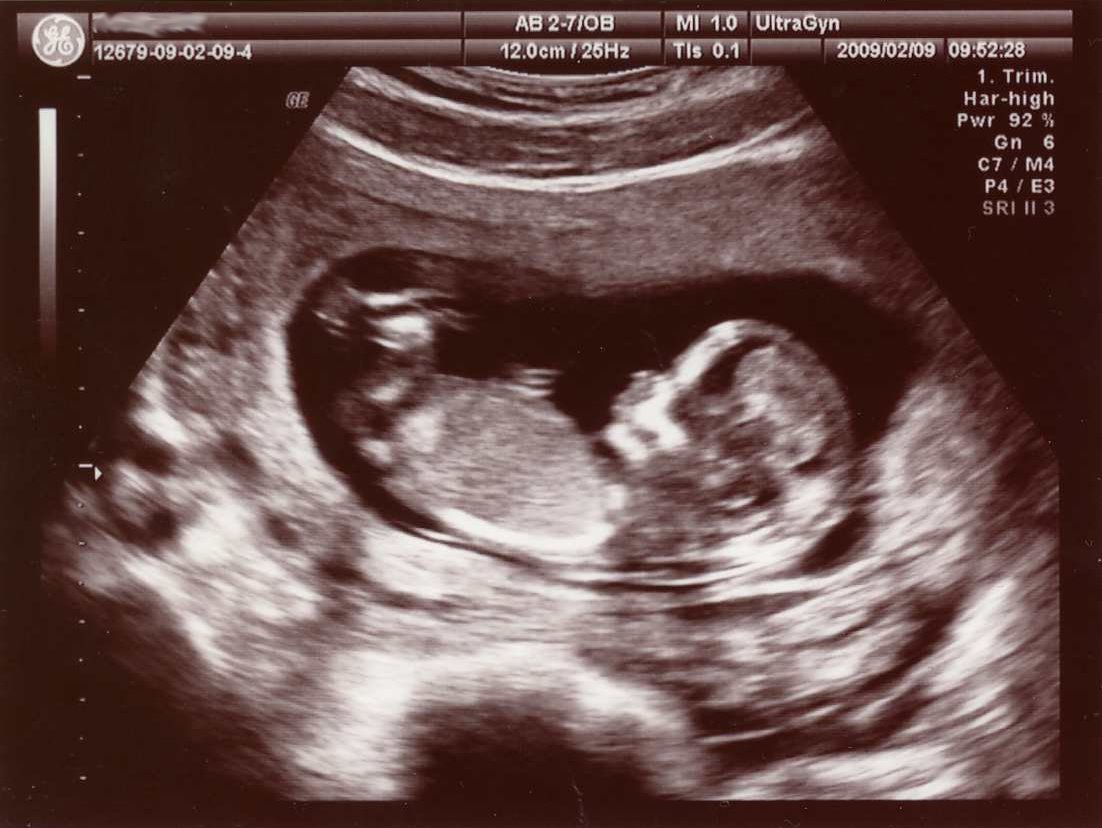

Jag har en känsla av att man kommer att få höra detta ett par gånger, och det är lugnt. Min son eller dotter (vi vet inte ännu) kommer ju i alla fall heta samma sak som mig, och vad det lider så kommer även Katty att göra det. Så då blir vi en familj.